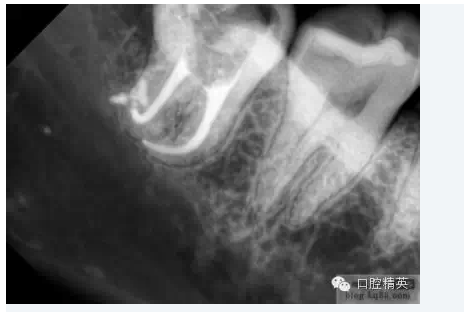

3.根管擴大器械可以很明確的告訴我們整個根管系統(tǒng)的解剖情況。臨床牙醫(yī)需要對整個根管系統(tǒng)都非常熟悉,包括其根管的彎曲、分叉、融合等等。此時根管擴大器械的根管探測作用即可派上大大的用場。它可以為我們提供非常詳細的資料:包括根管彎曲的部位及程度、根分叉的位置及分支多少。在應(yīng)用機用擴大針之前,牙醫(yī)必須了解根管的解剖情況:究竟是在髓腔部位只有一個而在下方分為兩個甚至更多,還是在髓腔部位是幾個而在下方發(fā)生融合甚至有時情況更加復(fù)雜:如從髓腔部分向下依次為幾個根管向下融合為一個然后又發(fā)生分叉現(xiàn)象等。只有對整個根管系統(tǒng)的解剖結(jié)構(gòu)有了非常清楚的了解,并能確定已達到應(yīng)用機用擴大針的條件,才有了成功的根管治療的基本保證。

當根管的髓腔向2/3的擴大完成以后,臨床牙醫(yī)即可順利的進行根尖1/3的擴大及最后精細完成。因為大部分的牙根彎曲及分叉都發(fā)生在該區(qū)域,所以,應(yīng)先應(yīng)用小型的不銹鋼可彎曲的根管擴大針對其進行小心而精密的探測,以獲得更詳細而準確的診斷資料。

1.根尖孔部位的預(yù)備小型的擴孔銼能為我們提供關(guān)于根管尖端1/3解剖結(jié)構(gòu)的準確信息,預(yù)先擴大的根管髓腔側(cè)2/3可以保證經(jīng)過預(yù)彎的小型擴孔器械自由出入,從而獲得關(guān)于根管尖端1/3解剖結(jié)構(gòu)的更明確的結(jié)論。正常情況下,根管系統(tǒng)會有一些根分叉、融合、彎曲等變異現(xiàn)象,甚至在同一部位同時出現(xiàn)幾種變異,此時對操作的要求就更高了。